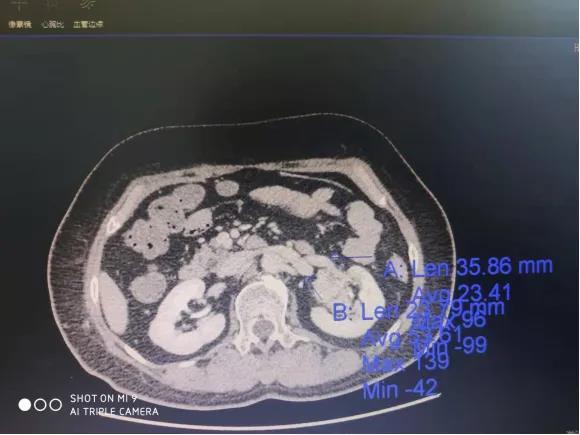

患者,女性,61岁,因体检发现左肾肿物一周收入院,入院后行全腹部增强CT检查回报:左肾下极肿瘤。大小48*47mmhg,肿瘤分期:T1bM0N0,肿瘤位于肾实质深部,上极紧贴肾门,各期影像显示患肾血供复杂:包括肾动脉、副肾动脉各一支。

肾静脉两支

变异血管分布如下:

第四腰椎椎前血管发出的侧支动脉一支

穿过后腹膜入肾上极变异动脉一支(来源于脾动脉)

肿瘤回流静脉一支(内有癌栓)